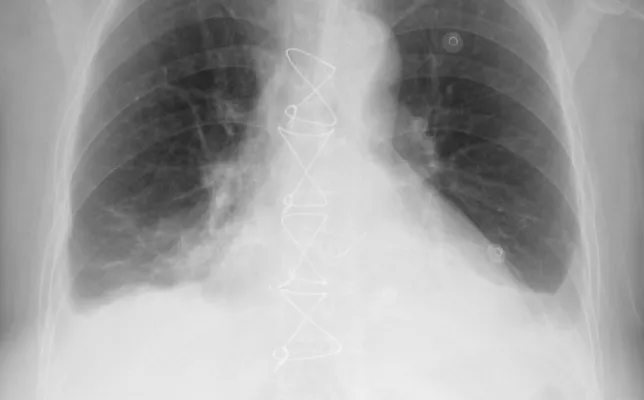

Los casos clínicos presentados corresponden a ejemplos seleccionados de la práctica radiológica, con fines educativos y de actualización profesional. Cada caso incluye hallazgos relevantes, diagnóstico diferencial y comentarios orientados al razonamiento radiológico. Todo el material ha sido anonimizado y se publica respetando los criterios de confidencialidad y privacidad del paciente.